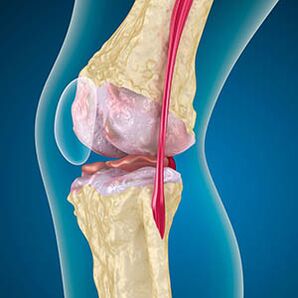

Artrosez, hezurretako ertzak estaltzen dituen kartilagoak urradura edo erabat falta da. Kaltetutako ehunak ez dira mina iturri bat, ez baitu hartzailerik. Inguruko egituretan hanturak sintoma bereizgarriak eragiten ditu.

Gorputzak kaltetutako ehunen birsorkuntza jarraitzen du, baina kartilagoa modu irregularrean hazten da. Ondorioz, arloko beste elementu batzuk zauritzen dituzten irregulartasunak eratzen dira. Ostefitoen izaera kartilago bateratuaren konpentsazioaren bidez azaltzen da. Beste bertsio batek "Spurs" hazkundea adierazten du Muskulu ahultzea dela eta, juntura etetea edo albokoa egonkortzeko saiakera batekin lotuta dago.

Hantura ehun bigunen, tendoien hantura eta poltsa bateratuko lesioak eragiten ditu. Belauneko beroaren itxura, hanturak hanturazko exudatoaren metaketa adierazten duArtrosia maiz bursitis, sinovitak, tendinitisa lagunduta dago.

Erradiografiak osteofitoen presentzia erakusten du, femoralen eta tibiako hezurren arteko espazioaren aldaketa, eta horrek kartilagoaren galera adierazten du belaunean. Batzuetan, belauneko artikulazioen X -Ray kartilagoen higaduraren seinale garrantzitsuak erakusten dira, baina gaixoek ez dute minik izaten.Aitzitik, lehen etaparen artrosiak belaunaren funtzioa eten dezake, minaren kausa gihar hipotonikoak baitira.